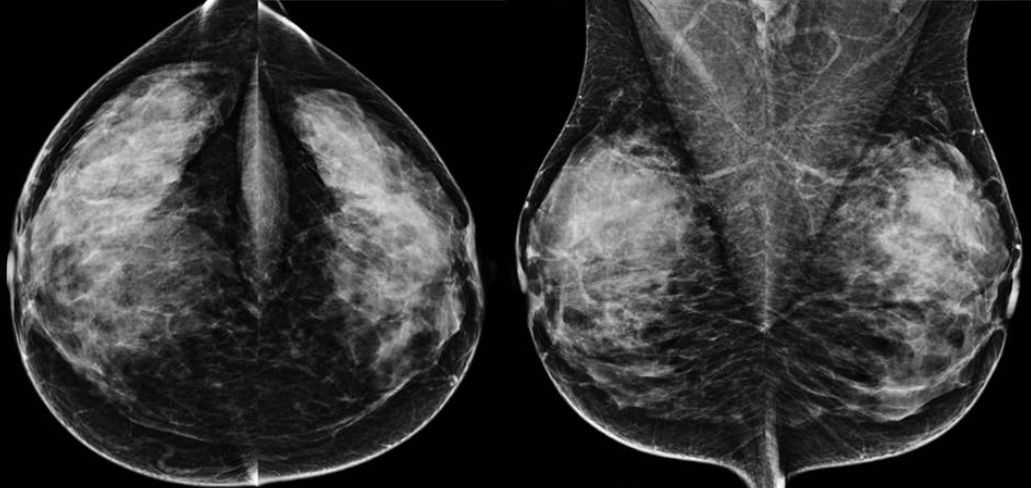

Kontrastmittel-Mammographie: Low-Energy-Bild